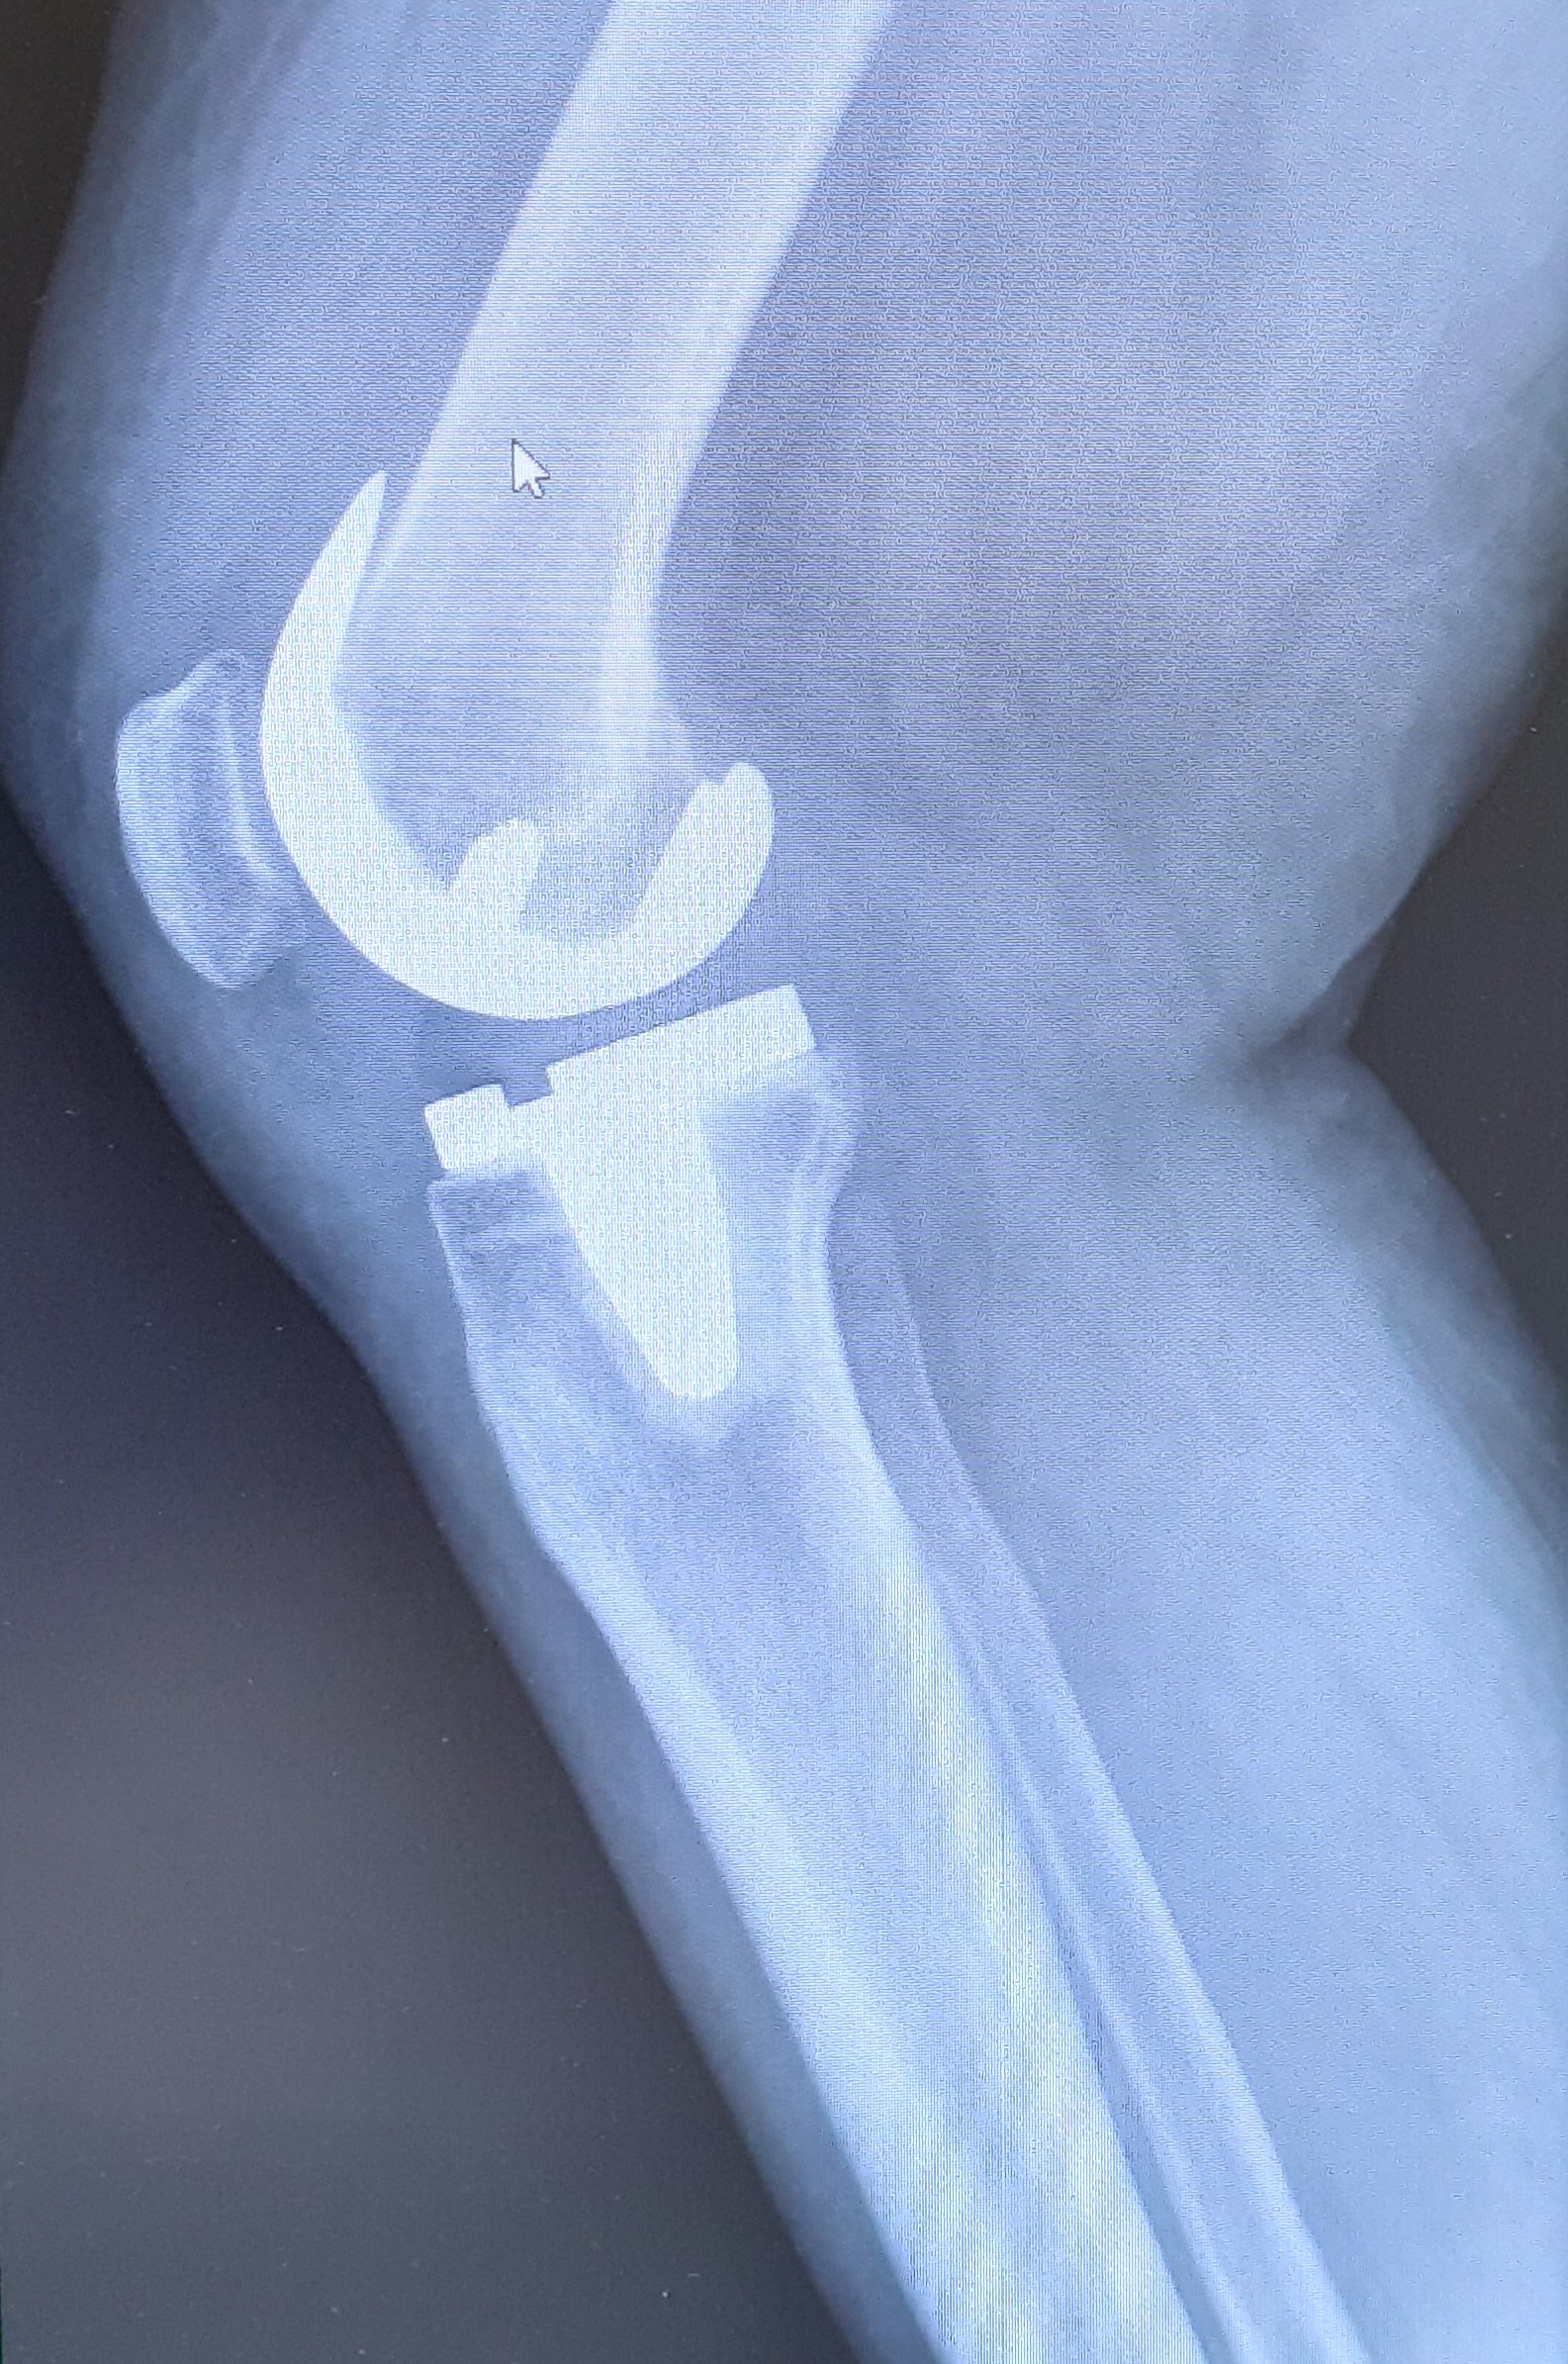

Therapie

Vorerst steht die konservative Therapie im Vordergrund mit dem Ziel einer Schmerzreduktion und einem beweglich machen des gereizten Kniegelenkes. Abschwellende Maßnahmen wie Eis und Topfen und die Einnahme von schmerz- und entzündungshemmenden Medikamenten sollten in dieser Phase angewendet werden. Auch Kniegelenksinfiltrationen können verabreicht werden. Ebenso kann ein Gelenksschmierenersatz mit Hyaluronsäure, welche in das Gelenk gespritzt wird, angewendet werden. Alternativ kann bei jungen Menschen auch eine ACP (autologes conditioniertes Plasma) in Erwägung gezogen werden.

Ein weiterer Pfeiler der konservativen Therapie sind physikalische Maßnahmen mit Heilgymnastik und Muskelaufbau.

Bei einer Achsfehlstellung kann diese ggfs. mit Einlagen teilweise korrigiert werden.

Bei fortgeschrittener Arthrose des Kniegelenks und entsprechendem Leidensdruck ist der künstliche Kniegelenksersatz die Therapie der Wahl. Dabei werden zunächst die geschädigten Knorpelanteile schablonenhaft entfernt und die Gelenkflächen mit Metallflächen ersetzt. Diese Metallflächen artikulieren über einen Mittelteil aus hochvernetztem Kunststoff, dem sogenannten Inlay.